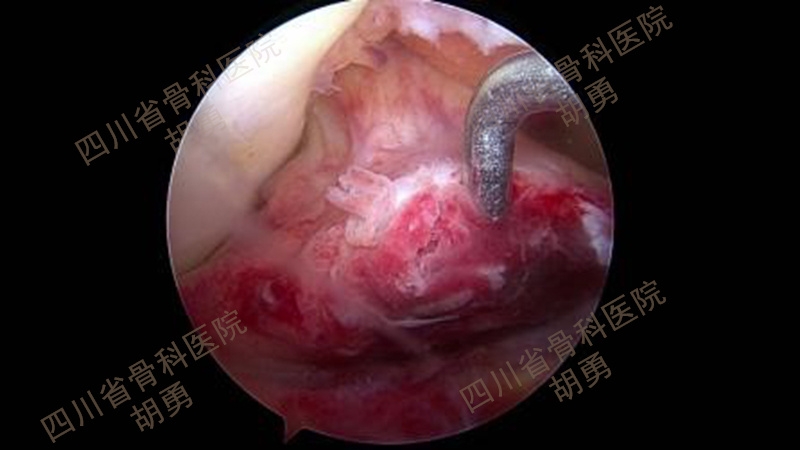

从2016年4月~2020年12月,共计25名4~11岁患儿接受了镜下手术,平均年龄9.2岁。在全部患儿中,有10名病程超过两周,属陈旧性骨折。作者采用了肩袖的镜下缝合桥技术,通过术中透视,所有的操作均在生长板上完成:在骨床后壁胫骨内、外侧髁间嵴连线中点植入一枚内排锚钉,用成角90°半月板全内缝合器将0号PDS线环在前叉韧带后内、后外两侧穿过撕脱骨块,将锚钉自带两种颜色的双骨科高强缝线分别从前叉韧带两侧过线穿过线环,并牵拉穿过撕脱骨块到达骨折表面。再将双色缝线混合引入胫骨骨床提前钻好的两个骨隧道中,双向交叉压迫于撕脱骨块上,调整骨位及缝线位置并拉紧缝线后,完成镜下复位。拉出胫骨隧道后的缝线使用一枚外排钉固定于生长板上。术毕,镜下缝线桥复位及内固定如图1所示,术前及术后MRI如图2和图3所示。术后2~3天,在疼痛缓解的前提下,开始主动康复训练。

图1 缝线桥复位及内固定术后镜下所见

将拉出入口备用的前内及前外骨隧道PDS线环分别引入关节内,使用环钳穿过线环,引入两色骨科高强线各一根,从胫骨隧道拉出线环,将两色缝线各一根混合引入前内及前外骨隧道,如图19所示。调整撕脱骨块骨位及交叉压迫于骨面的缝线位置和牵拉张力后,镜下所见如图1所示。